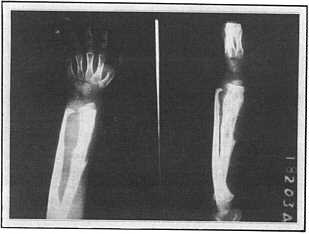

Ewing's sarcoma of the bone before treatment

bntumorx.jpg (7546 bytes)

after treatment

Bone cancer can occur as a primary disease, or as a secondary tumor when other cancers metastasize.  A case of the former, Ewing's sarcoma of the bone in a young child, is presented in the 1990 patent.

The same case is presented in more detail in Clinical Experience with the Practice of  Insulin Potentiation Therapy: Best Case Series by Donato Perez Garcia y Bellón, M.D.,  Donato Perez Garcia, Jr., M.D., and  SGA, M.D. (1997), and in Insulin and cancer chemotherapy (SGA, M.D., unpublished article, 1987.